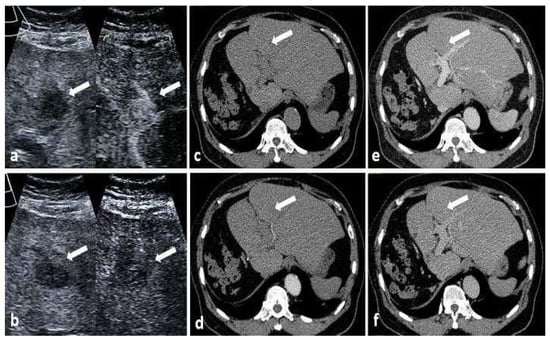

3.2. CEUS LI-RADS Features between Different Nodule Characteristics and Liver Background

3.3. Comparison between CEUS and CT/MRI on LI-RADS Major Features for Recurrent HCC